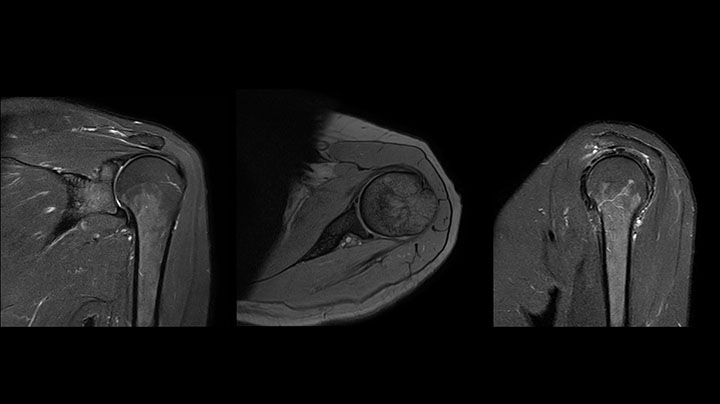

Shoulder MRI with high quality, large coverage

The Prodiva shoulder coil is very flexible and has large coverage, which makes good positioning easier, and that contributes to the superb image quality and high SNR that we get in our shoulder exams.

Scan time 2:55 min, FOV 160 mm,

acq voxels 0.55 x 0.83 x 3.0 mm.

Scan time 4:19 min, FOV 160 mm,

acq voxels 0.55 x 0.80 x 3.0 mm.

Scan time 2:50 min, FOV 160 mm,

acq voxels 0.70 x 0.99 x 3.0 mm.

Shoulder MRI with high quality, mFFE

Shoulder MRI with high quality, STIR TSE